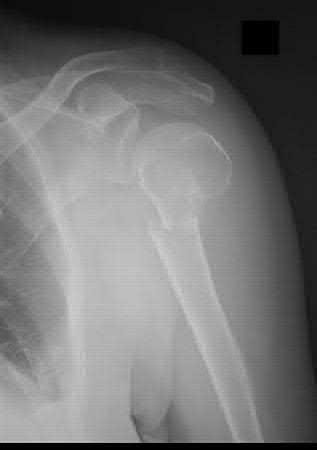

A 55-year-old patient presents with a slowly enlarging, painful mass in the proximal humerus.

Biopsy reveals a hyaline cartilage matrix with cellular atypia, confirming a diagnosis of central conventional chondrosarcoma. Which of the following genetic mutations is most frequently identified in this specific tumor?

Explanation

Mutations in the isocitrate dehydrogenase genes, IDH1 and IDH2, are found in up to 50-60% of central conventional chondrosarcomas and enchondromas. EXT1 and EXT2 mutations are characteristic of multiple hereditary exostoses (osteochondromas). GNAS mutations are seen in fibrous dysplasia. TP53 and RB1 mutations are hallmark aberrations in osteosarcoma.